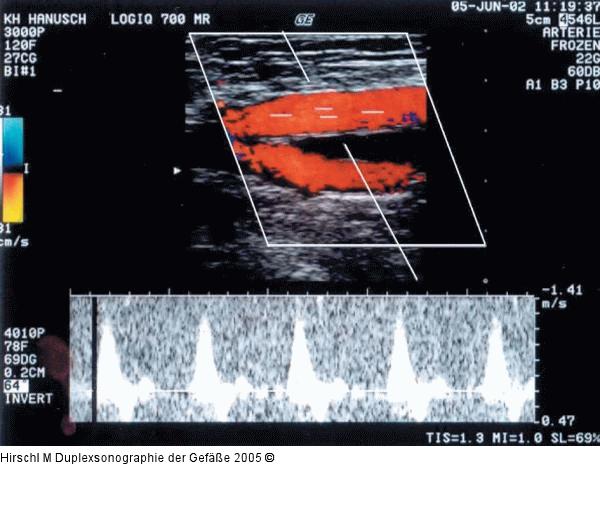

Abbildung 15: Duplexsonographie - Pulsdoppler

Übersteuertes Dopplergain mit massivem Hintergrundrauschen. |